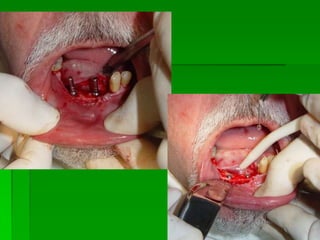

PRIMEIRA FASE CIRÚRGICAMOTOR PARA CIRURGIAPRIMEIRA FASE CIRÚRGICAKITS CIRÚRGICOSTipos de implante e indicações

Seqüência de Brocas

Avaliação Clínica no Momento da Instalação do ImplanteAparelhos especiais Osstell (mede por freqüência e ressonância)Avaliação Clínica (estabilidade)Torquímetro (mínimo 45 Newtons)Avaliação   radiográfica   ( durante   a instalação,  mede  a  distância   entre implantes e estruturas adjacentes)

Implantes